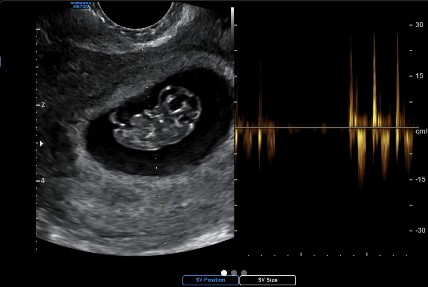

1일 고우리는 자신의 소셜 계정에 “네 저 임신했어요. 안정기가 될 때까지 조심 또 조심하느라 조용히 시간을 보내고 있었답니다”라는 글과 태아 사진을 공개했다.

사진에서 고우리는 태야 사진과 함께 심장 박동 소리도 공개했다. 고우리는 태명이 ‘복덩이’라고 밝히며 “앞으로 별탈없이 건강하게 태어나도록 많은 응원과 사랑 부탁드려요. 그럼 여러분들도 복 많이 받으실 거예요”라고 말했다.